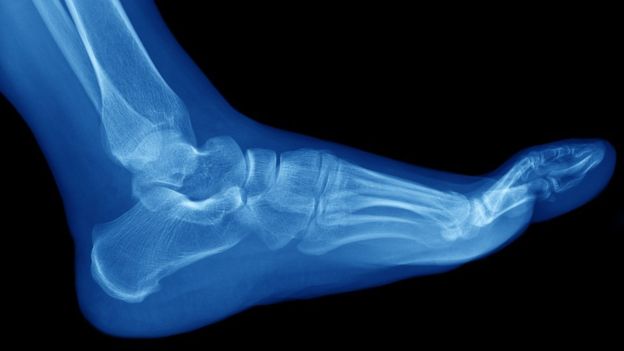

Las fracturas por estrés suelen ocurrir en los huesos de la parte inferior de la pierna y el pie, como la tibia y el peroné, los metatarsos, el talón y el tobillo. GETTY IMAGES

Las fracturas de hueso que la mayoría de la gente conoce son debidas a un golpe traumático. Pero hay otro tipo de lesiones, llamadas fracturas por estrés, por esfuerzo o por fatiga, en las que se generan pequeñas roturas o micro traumatismos en los huesos debido al impacto repetitivo del sobreuso. Lea más